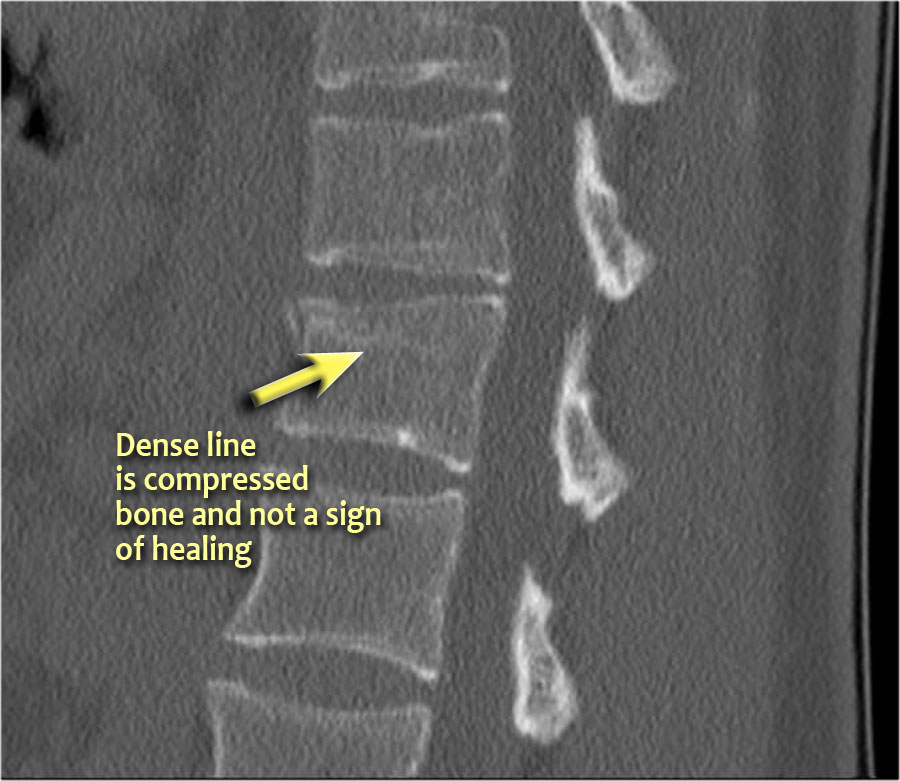

Lưu ý dải tăng tỷ trọng theo chiều ngang, thường được mô tả là xơ cứng (sclerosis).

Dải tăng tỷ trọng này không có nghĩa là tổn thương cũ đang lành với xơ cứng.

Đây đơn thuần là dấu hiệu của sự chèn ép bè xương (trabecular impaction) trong gãy xương cấp tính.

Rất thường gặp trường hợp CT và MRI phát hiện nhiều ổ gãy xương hơn so với X-quang thường quy.

Trong trường hợp này, CT phát hiện 2 ổ gãy và MRI phát hiện 3 ổ gãy.